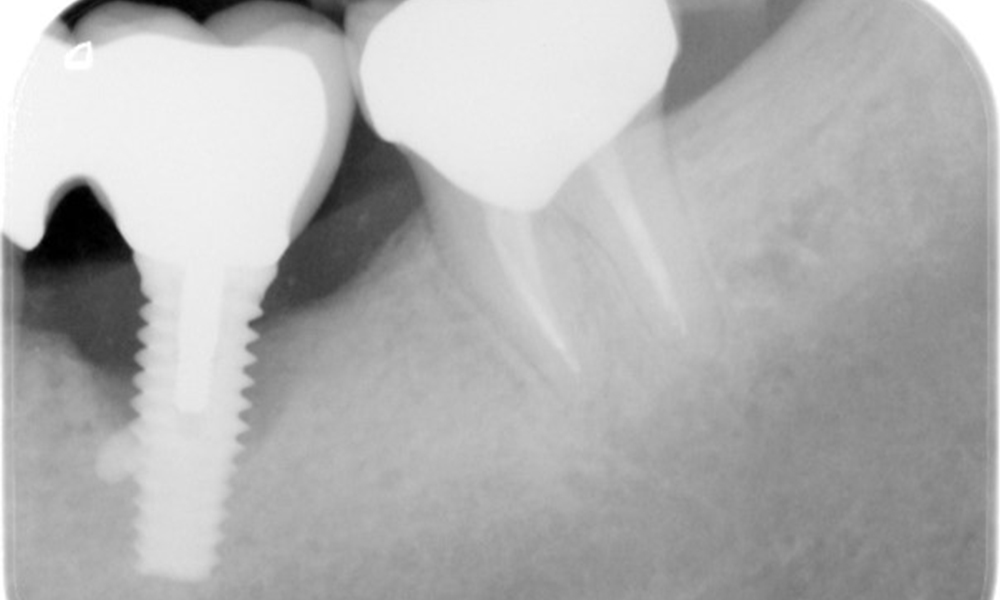

The patient has no particular risk factors with specific dental implications in his medical history. The key factor, therefore, is the requirement in terms of oral health. In this respect, there is evidence of a probing depth of 5 mm at the implant in the 3rd quadrant and, on the X-ray image, increased bone loss. The patient also has currently stable early periodontal disease and two active initial carious lesions.

The X-ray images show the progression of bone loss.

The X-ray images show the progression of bone loss in the area of the implant in region 36: dental film from 11.02.2021 (left) and dental film from 18.01.2024 (right).